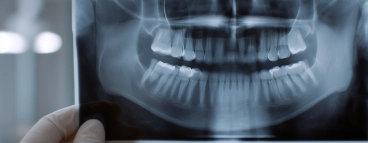

Контроль и анализ проведенных методов показали реальные сроки восстановления костной ткани в патологических околоверхушечных очагах деструкции. Стоматологи терапевты проявляют искренний интерес к пациенту и состоянию его здоровья: при диагностике делаются необходимые рентгенограммы, проводят тщательное стоматологическое обследование, помогают в постановке правильного диагноза. Регулярные контрольные осмотры позволяют своевременно выявлять проблемы. Результаты высококачественного стоматологического лечения сохраняются в течение продолжительного времени.